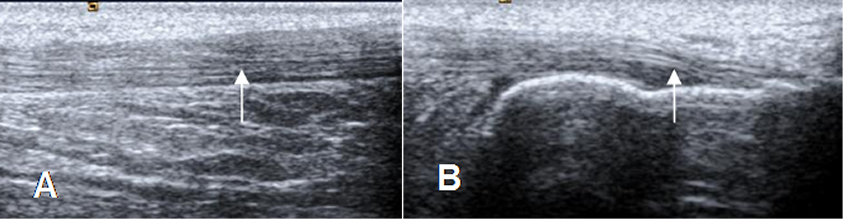

Fig 22. Tendón de aquiles normal en ecografía, corte sagital.

A: Tercio medio y B: En su inserción.

Fig 23. Tendón de aquiles normal.

A: Ecografía transversa y B: RM axial en T1. Estructura ovalada y homogénea, cóncava anteriormente. En RM hay zonas hiperintensas, que corresponden a septos.